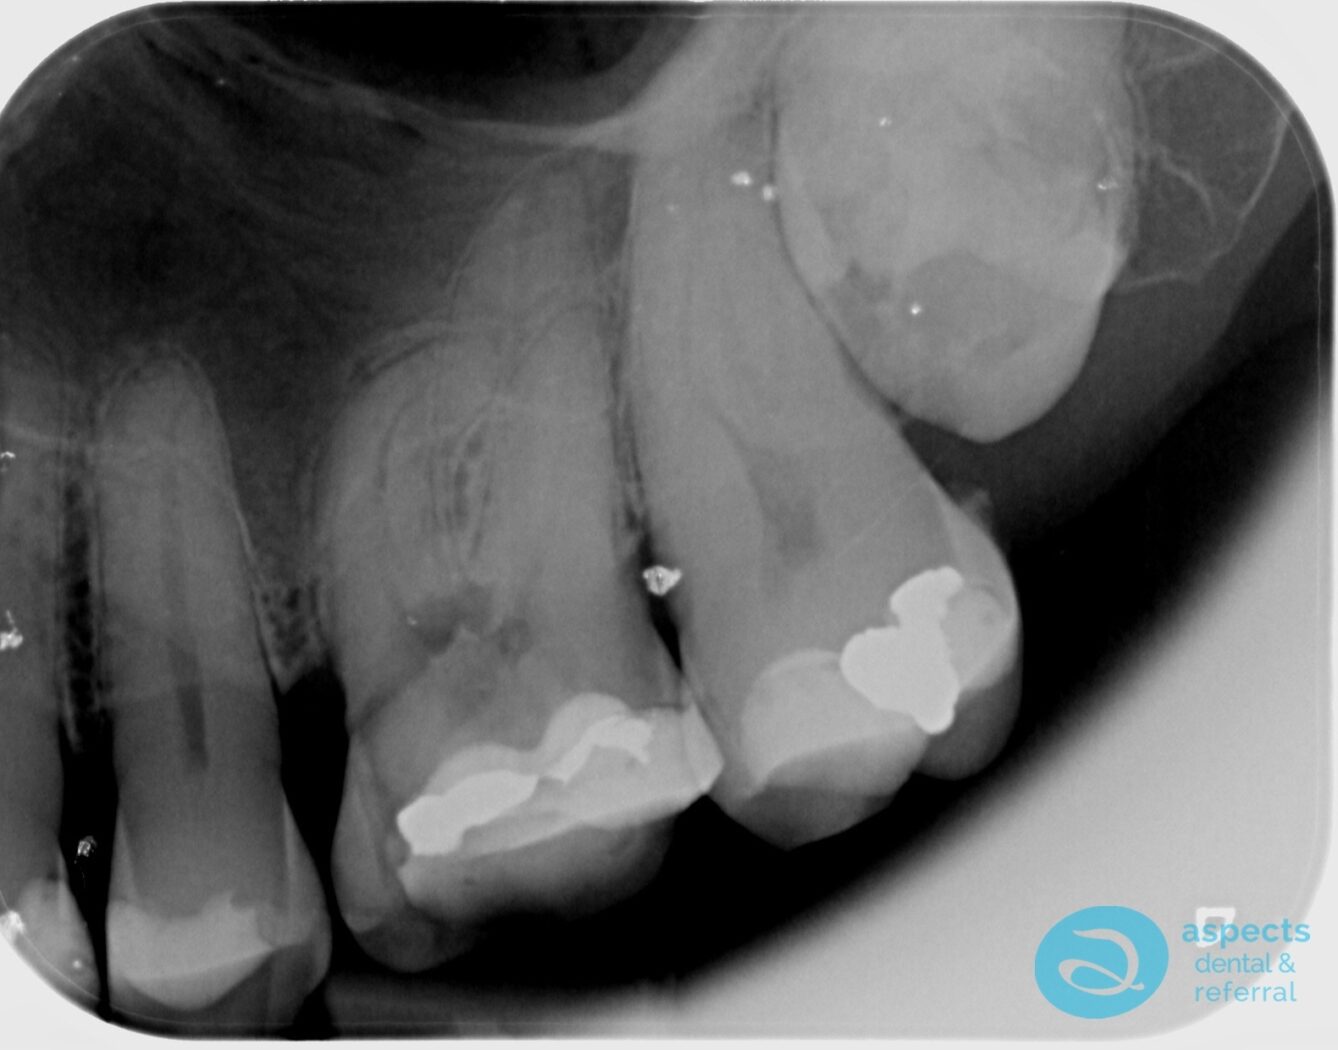

Before Tooth Extraction & Sinus Lift Xray